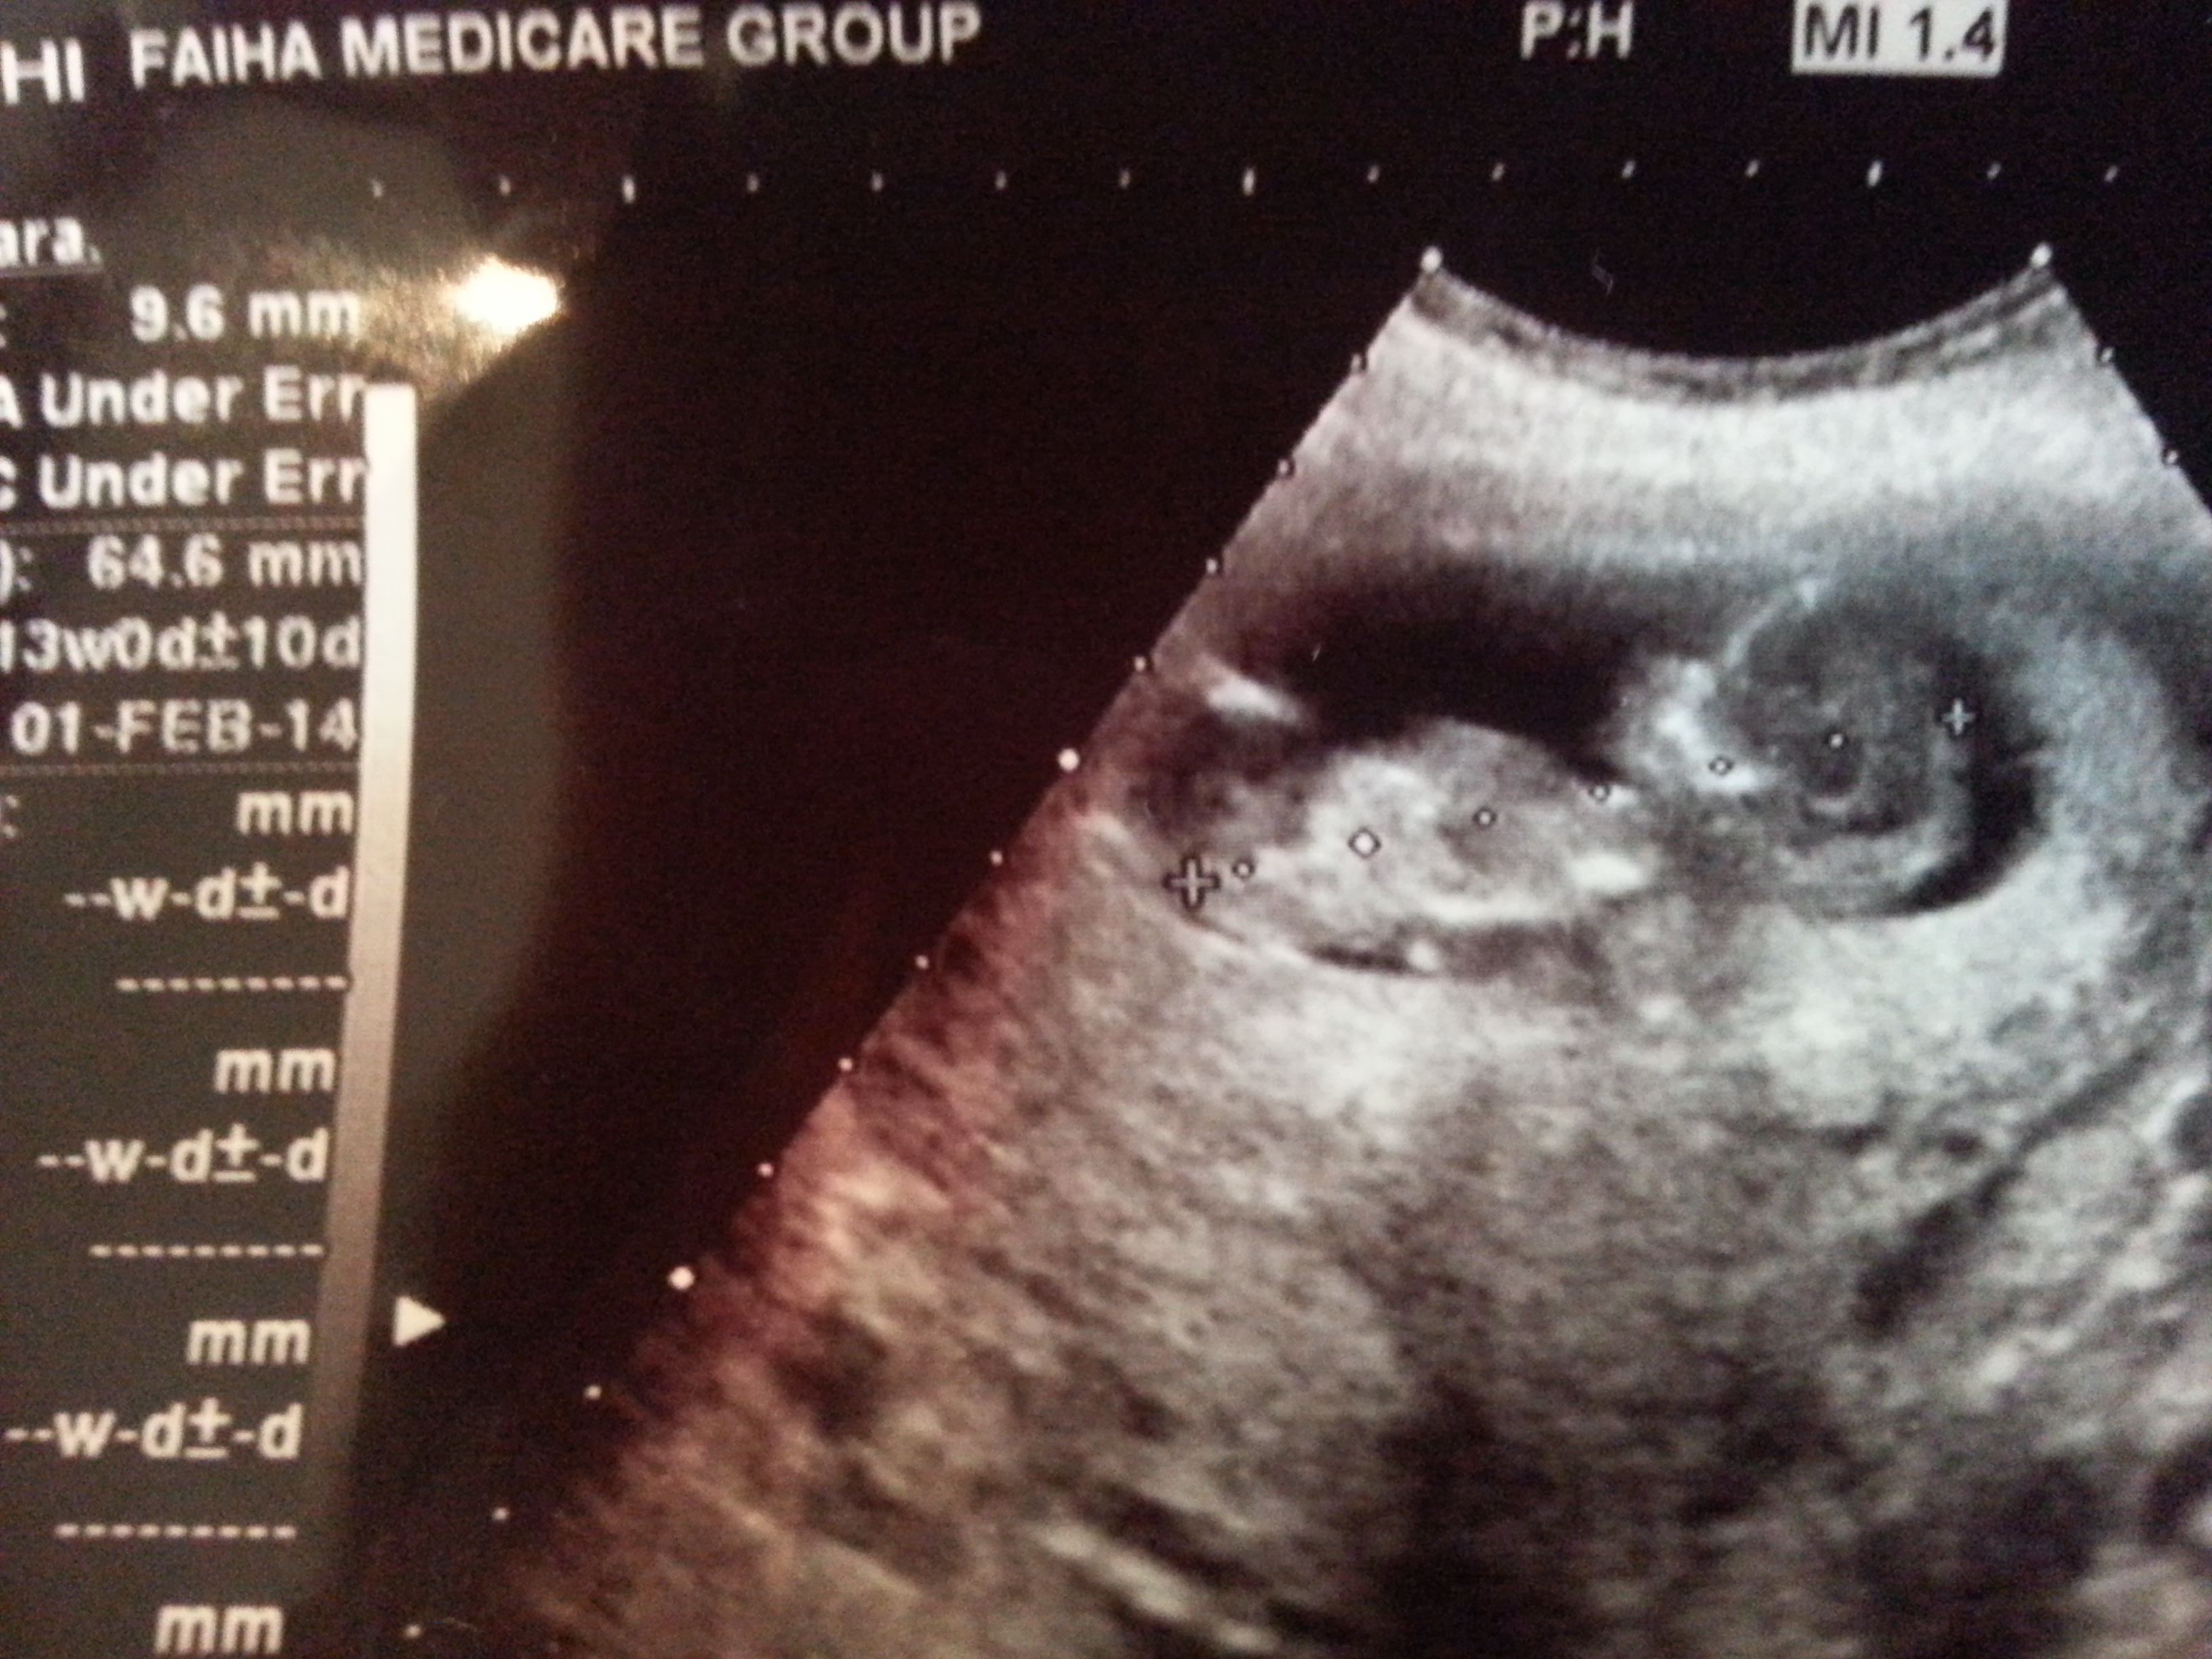

In Gender forum said it i not a nub .

It is a leg .

I know my pic is not clear and lacking focus .

please help I only need a guess!!

If its not the leg bone then I would guess boy... But I'm not sure if it's a nub or a leg

I think it is too high for a leg

Leg must be flat ;is not it ?!

Best guess from me is also boy, but super hard to tell. Might be a leg. Might not be either the nub or a leg. It's super blurry.

If it is nub, my guess is boy. Seems a bit short for nub.

I would guess boy, but the pic isn't very clear